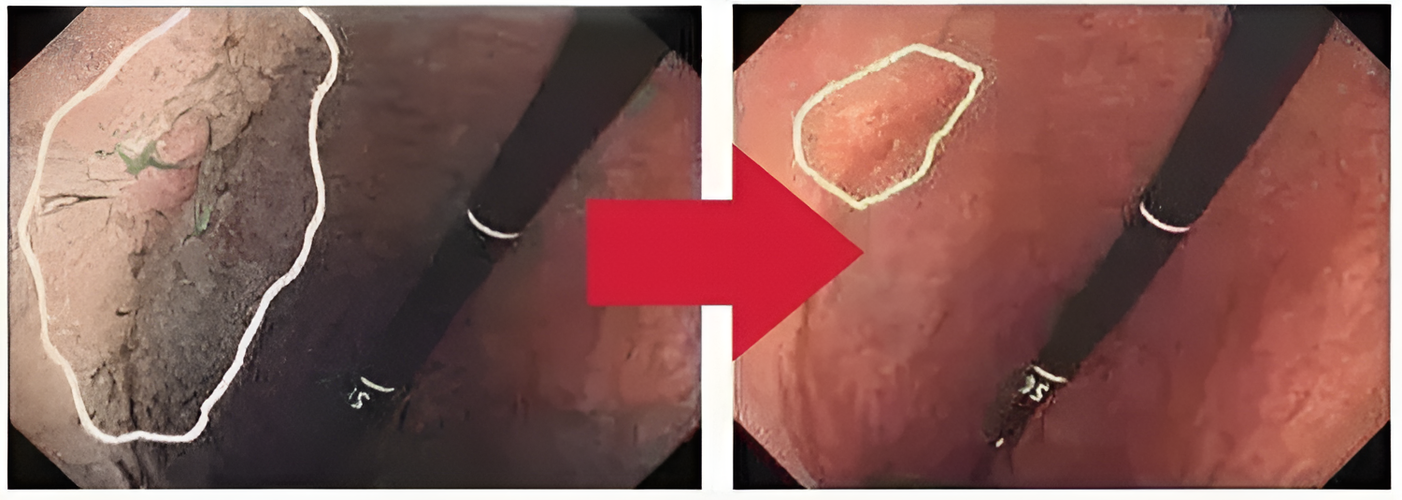

Moisturizing enteritis gel cares for the stomach and intestines, body and skin, and relieves discomf✨